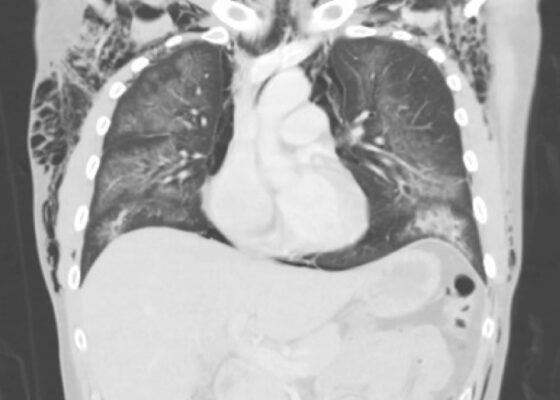

DOI: https://doi.org/10.21980/J8S65PThe CT of the chest with contrast showed subcutaneous emphysema (green star), pneumomediastinum (yellow arrow), and pneumopericardium (purple asterix) without an identifiable tracheal tear. Extensive air was visualized as hypodense areas within the chest wall within the soft tissue. The image also detailed a hypodense area surrounding the heart consistent with pneumopericardium. No disruption of the trachea was present. Additionally, the CT of the chest also showed bilateral ground glass airspace opacities (red stars) with subpleural sparing that is consistent with EVALI findings.2,5 These specific findings have been seen in many of the EVALI cases.5 This image is interesting because there is extensive pneumomediastinum with no clearly identifiable cause. The imaging shows no esophageal or tracheal or lung injury, so it is important to note relevant information collected during interview regarding patient’s recent history of vaping THC, especially when establishing a differential diagnosis.